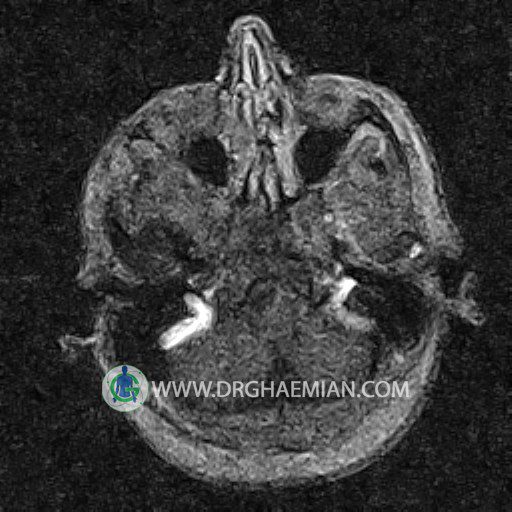

ام آر وی یک روش تصویربرداری دقیق و غیر تهاجمی است که برای معاینه ورید های بدن و ارزیابی سلامت رگ ها استفاده می شود. ورید ها خون را از اعضای بدن به قلب باز می گرداند تا دوباره اکسیژن و مواد مغذی به خون داده شود. ام آر وی جریان خون را ارزیابی و موارد غیرعادی مضر مانند لخته های خونی را شناسایی می کند. در این کیس ترومبوز دیواری مغز در سینوس عرضی راست و ترمبوز جزئی در سینوس عرضی چپ دیده می شود.

– Narrowing of left transverse sinus with filling defect & inthimal irregularity

suggestive for partial thrombosis

– Inthimal irregularity in anterior wall of right transverse sinus suggestive for mural thrombosis

are seen